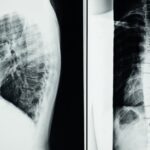

Les hernies discales constituent un problème de santé prevalent qui impacte directement la qualité de vie des individus. Elles surviennent lorsque le matériel gélatineux à l’intérieur d’un disque intervertébral s’échappe, exerçant une pression sur les nerfs environnants. Ce phénomène peut engendrer des douleurs aiguës, des engourdissements, ou encore des sensations de picotements dans les membres. La décompression neurovertébrale vise à réduire cette pression à travers des techniques de traction douce, créant ainsi un espace entre les vertèbres et permettant aux disques de retrouver leur position naturelle.

La décompression neurovertébrale utilise des techniques de traction douce sur la colonne vertébrale. L’objectif est de créer un espace entre les vertèbres, ce qui diminue la pression sur les nerfs ainsi que sur les disques intervertébraux. En réduisant cette pression, la décompression aide à soulager les douleurs neuropathiques chez les patients souffrant de hernies discales.

La décompression neurovertébrale repose sur l’application d’une traction douce sur la colonne vertébrale. Ce processus crée un espace entre les vertèbres, diminuant la pression sur les nerfs et les disques intervertébraux. En facilitant la circulation sanguine vers ces zones, la méthode aide à réduire l’inflammation et à promouvoir une régénération tissulaire efficace. Les patients peuvent souvent constater une amélioration significative de leurs symptômes après quelques séances seulement.